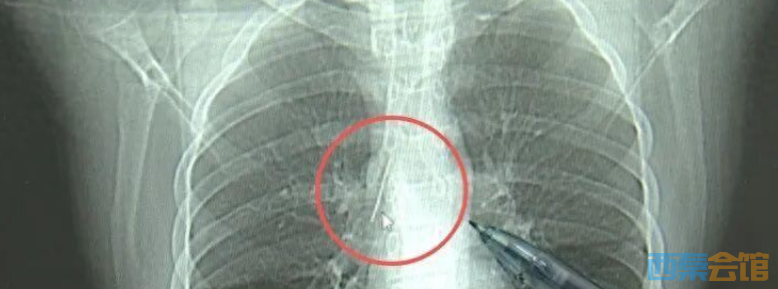

近日,安徽17岁小伙小陆参加征兵体检,胸片结果显示:胸腔内有一处金属高密度影,形态细长,像一根针。 进一步的CT检查确认,异物是一枚金属针,斜插在肺组织内,位置十分凶险。

杭州市第一人民医院心胸外科副主任 冯兴:“我们看到这个针的尖锐部,正好指向他体内的一个大血管,边上是上腔静脉和胸主动脉,因此这个针稍有不慎,就有可能造成周边血管的损伤,甚至危及生命。” 针到底是怎么来的?小陆父母反复回忆,终于想起孩子一岁多时,曾莫名哭闹得很厉害,当时孩子年龄小不会表达,也就不了了之了。 医生推测,那枚针很可能就是在那时候扎入体内的。针在小陆体内滞留了十几年,既没有引发感染,也没有造成气胸,堪称医学奇迹。上周四,医院为小陆实施了mini单孔胸腔镜微创手术,切口仅两厘米左右,成功将针完整取出。  来源:大象新闻综合南国都市报、杭州综合频道 (来源:大象新闻综合)